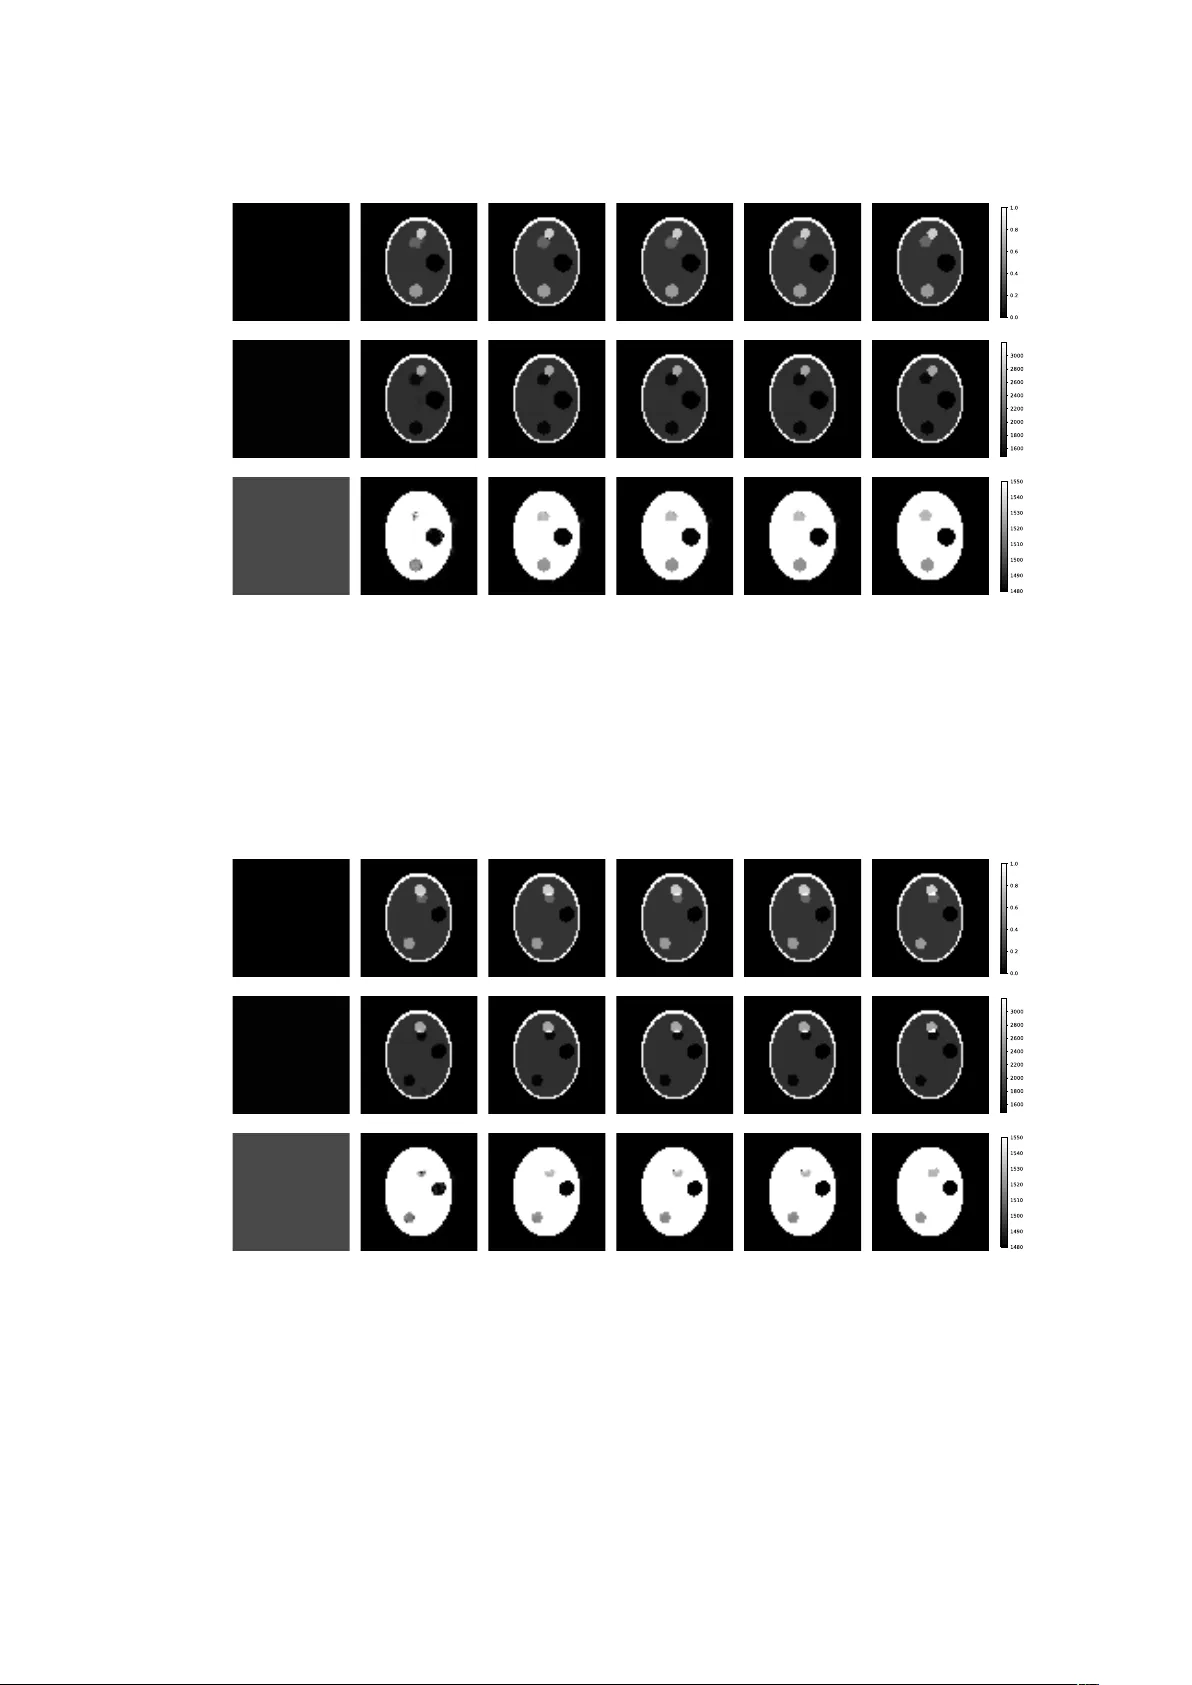

본 논문은 사진음향 단층촬영(PAT)에서 초기 압력과 조직의 음속 분포를 동시에 복원하기 위해, 전통적인 모델 기반 반복법에 딥 뉴럴 네트워크를 결합한 SR‑Net을 제안한다. 시뮬레이션 실험을 통해 초기 압력과 음속을 높은 정확도로 복원함을 확인하였다.

본 논문은 사진음향 단층촬영(PAT)에서 초기 압력(p₀)과 조직의 음속(c)을 동시에 복원하는 새로운 데이터‑드리븐 접근법을 제시한다. 기존의 대부분 PAT 재구성 알고리즘은 음속을 정확히 알고 있다는 전제 하에 초기 압력만을 역산했으며, 실제 임상 환경에서는 조직마다 음속이 다르고 사전에 측정하기 어렵다. 이러한 문제를 해결하기 위해 저자들은 모델 기반 최적화와 딥러닝을 결합한 SR‑Net(Simultaneous Reconstruction Network)을 설계하였다. 먼저, 파동 방정식(1)을 기반으로 측정 연산자 Λ(c, p₀)를 정의하고, 이를 통해 측정 데이터 g=Λ(c, p₀)를 얻는다. 고정된 음속 c에 대해서는 Λ가 선형이므로, p₀에 대한 선형 연산자 H(c)를 도출할 수 있다. 기존 연구